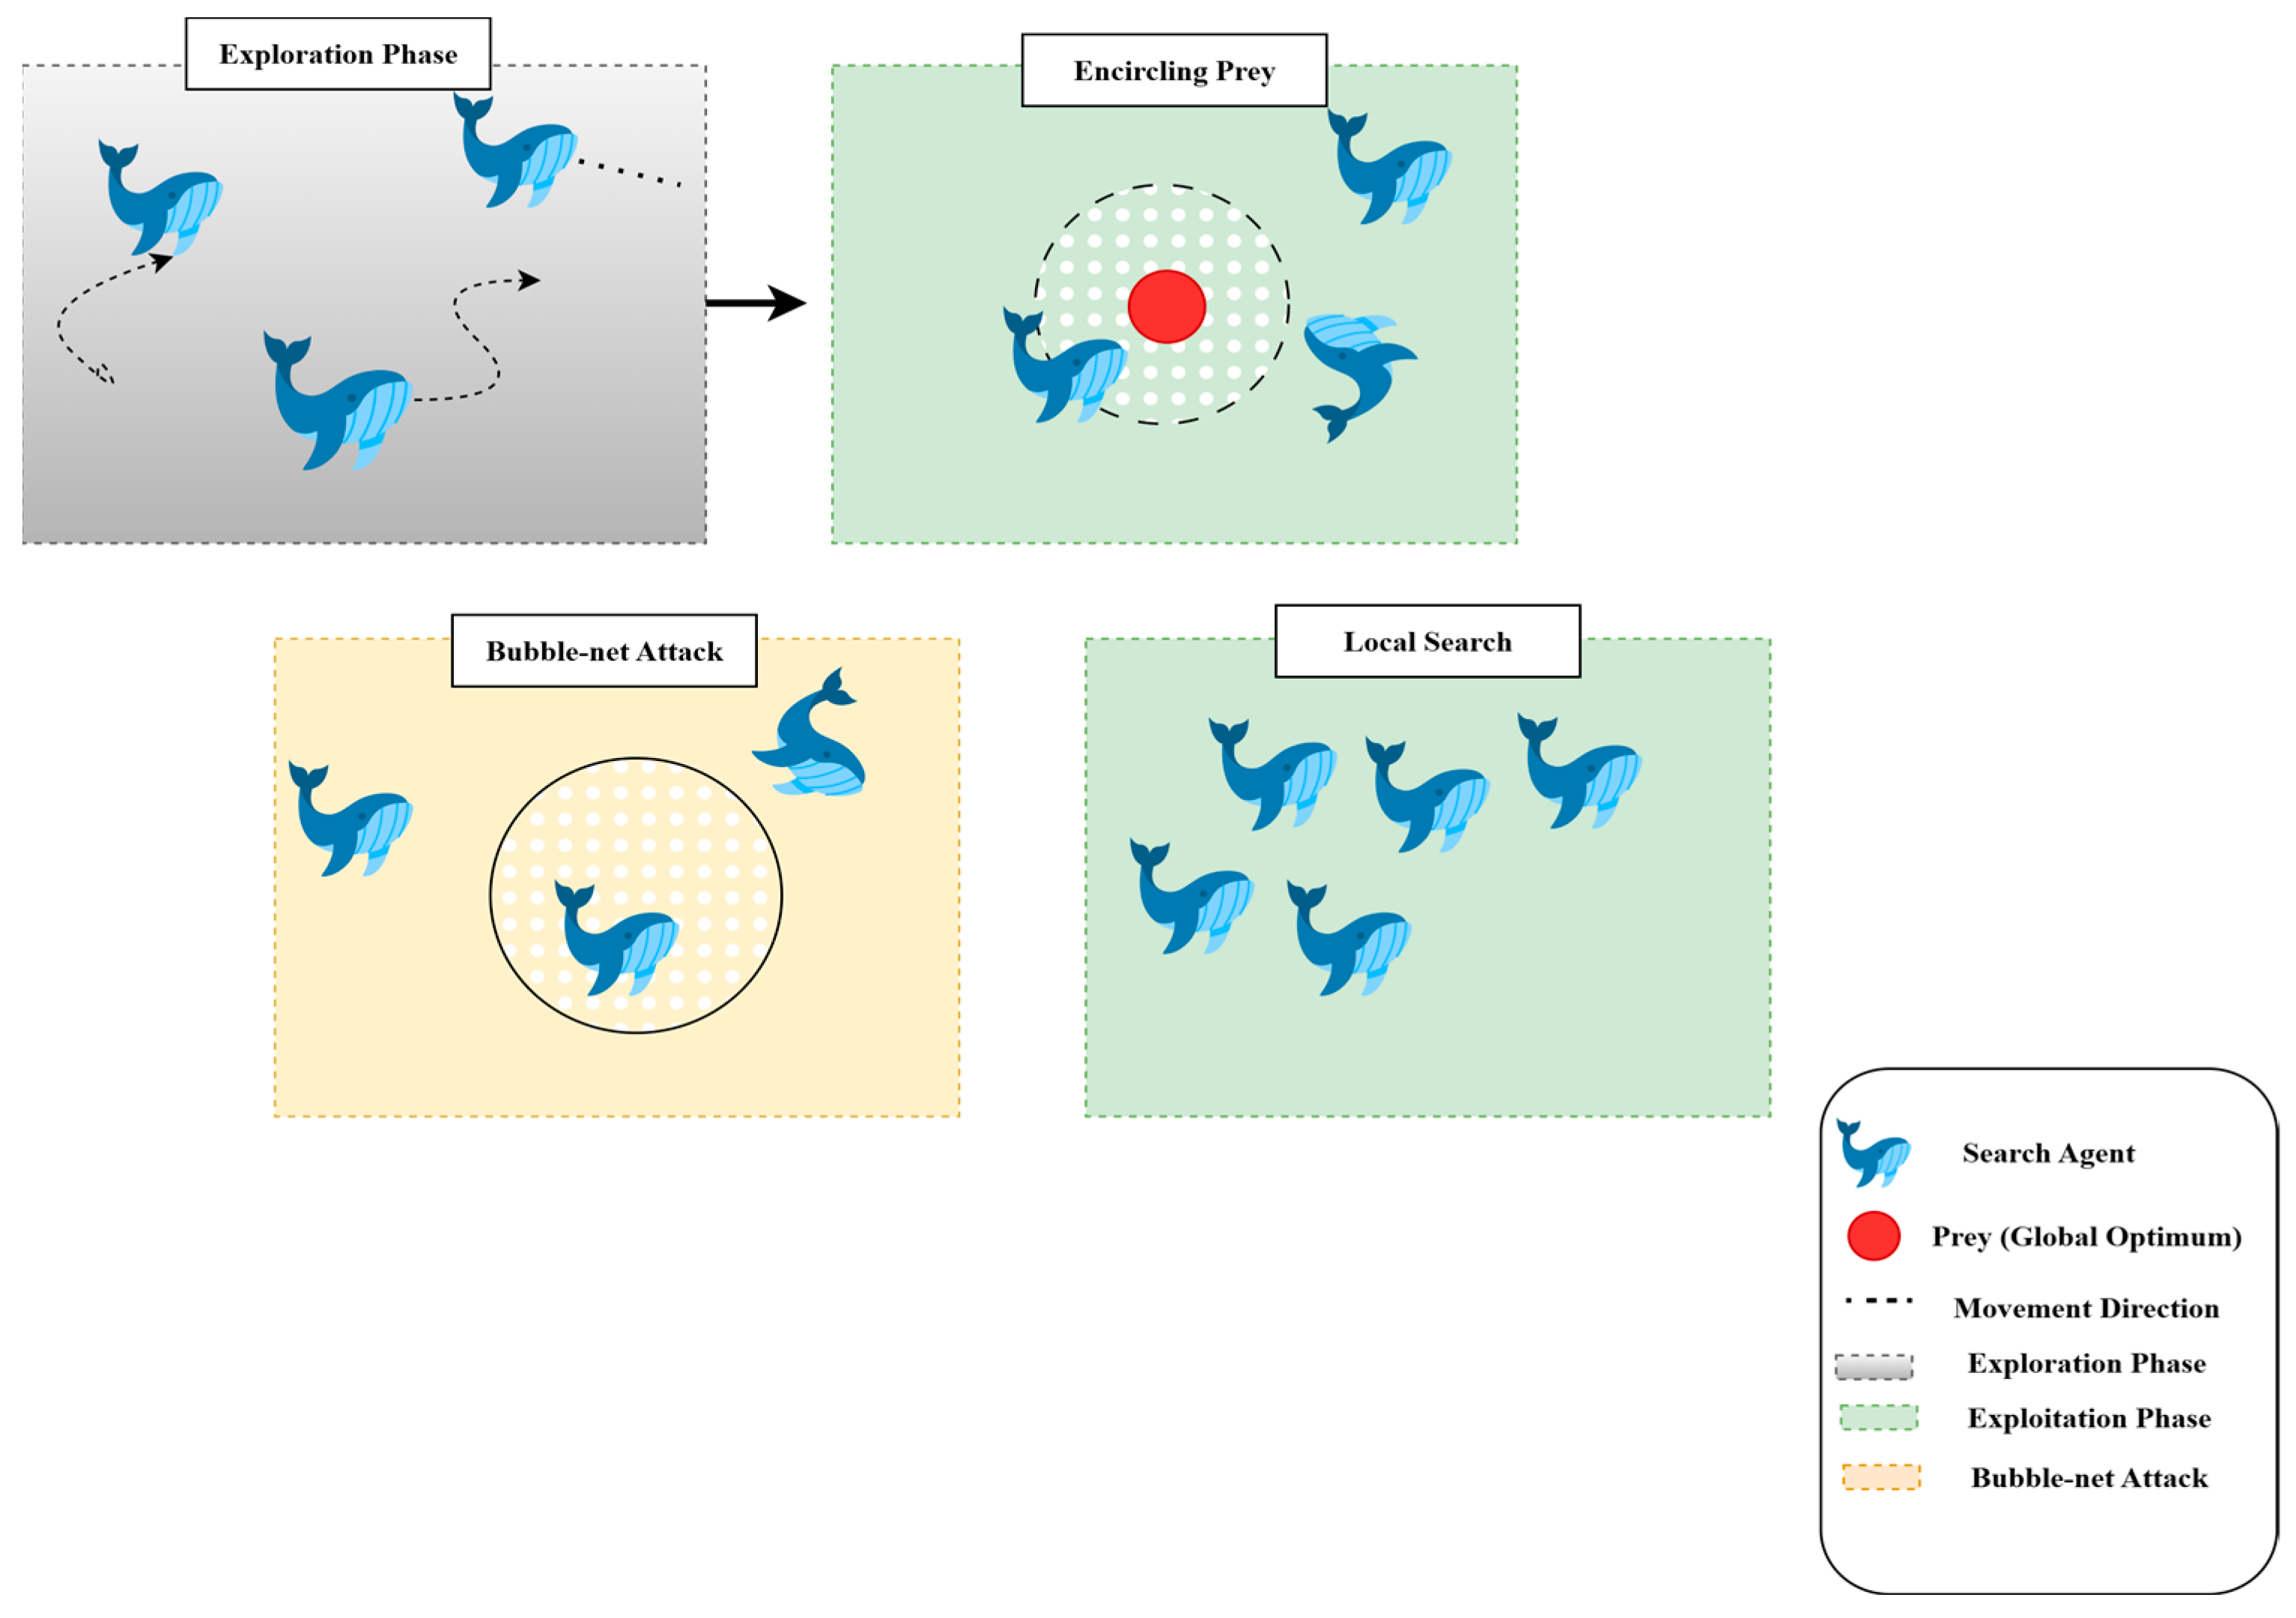

3.4. Swarm-Based Whale Optimization Algorithm (WOA)

3.4.1. Motivation from Nature

3.4.2. Exploration and Exploitation Phases

- Exploration: This process iteratively traverses the search dimensions in search of the global optimum. During this phase, whales move randomly to search for unvisited regions. The search is guided by the position of the best solution found so far, allowing the algorithm to escape local optima.

- Exploitation: This phase focuses on refining the search around the best solution detected. Whales use the shrinking (enclosing) mechanism along with the spiral path, updating their position by considering the spiral trajectory, which converges more effectively to the global optimum.